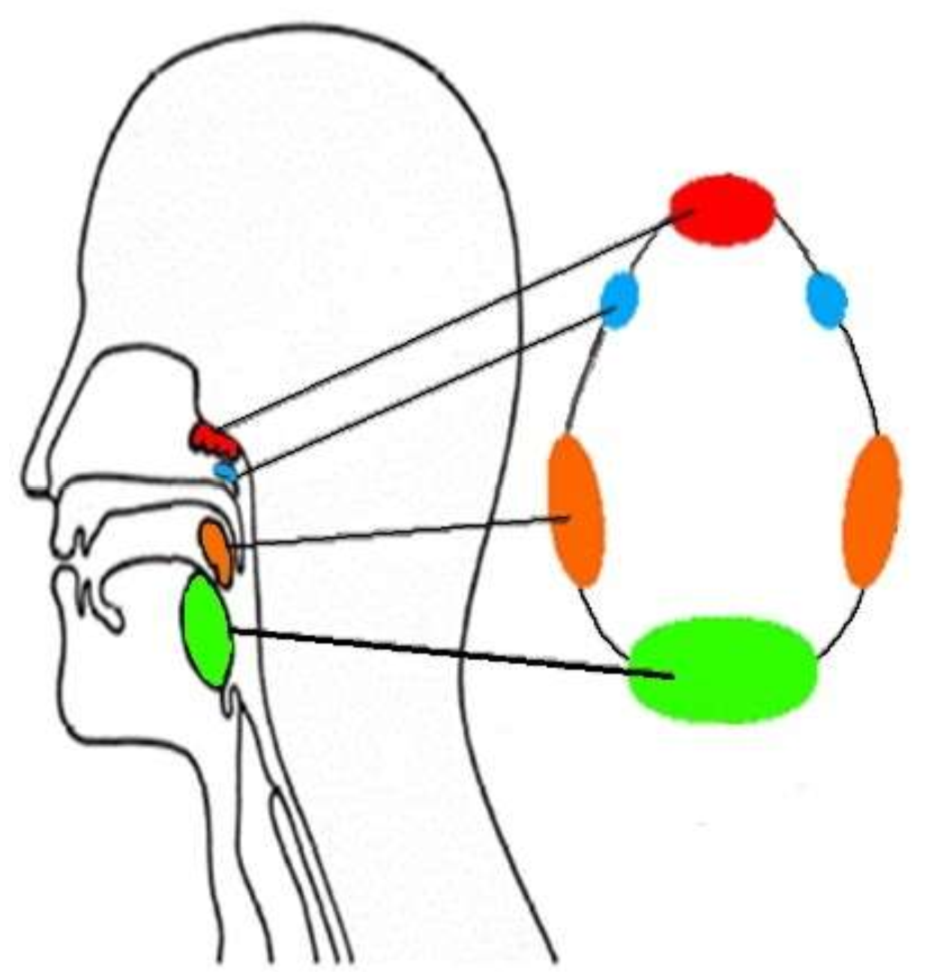

What is this group of structures called?

waldeyers ring

What is in red?

pharyngeal tonsil

What is in blue?

tubal tonsils

What is in orange?

palatine tonsils

What is in green?

lingual tonsil